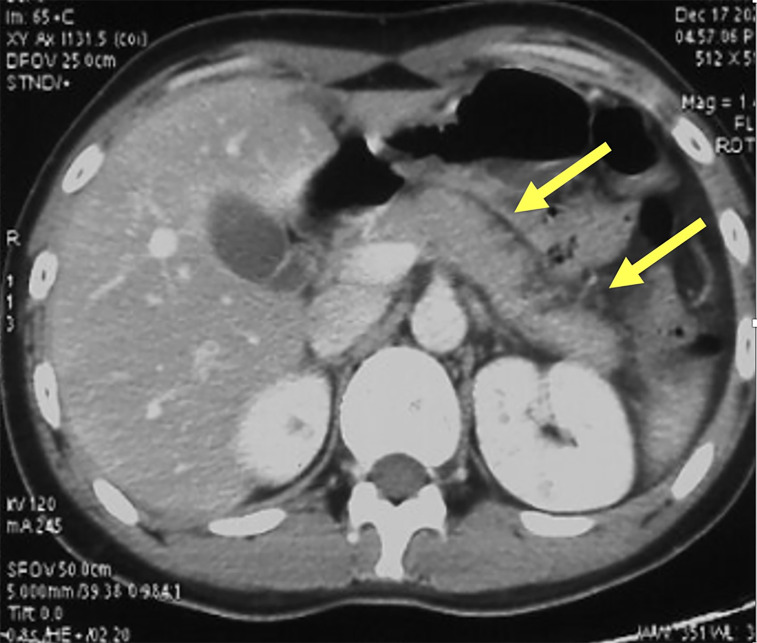

Rare cause of recurrent acute pancreatitis in teenage man.

青少年男性复发性急性胰腺炎的罕见病因。